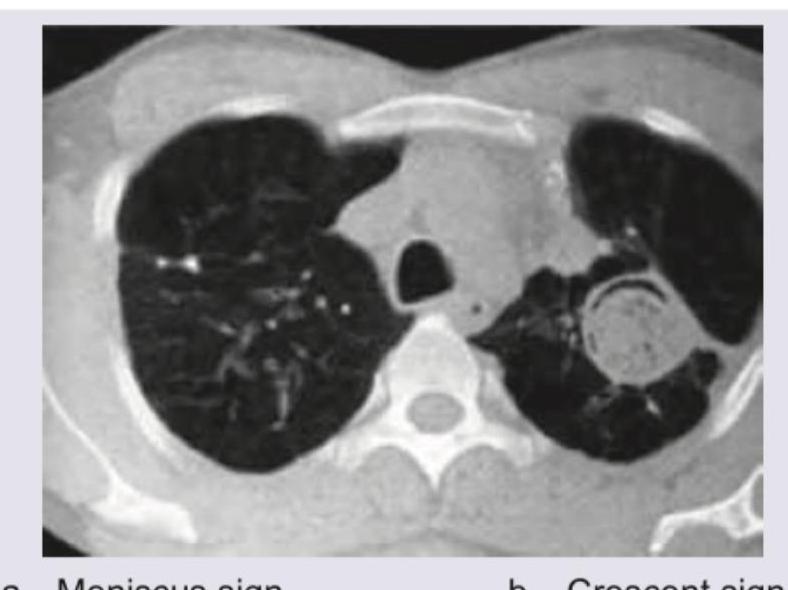

Explanation: ***Meniscus sign*** - The **meniscus sign** refers to the characteristic appearance of pleural fluid forming a smooth, curved interface with the lung parenchyma on imaging. - On CT chest, this appears as a **concave meniscus** (curved upward) where the fluid collection meets the adjacent lung, creating **obtuse angles laterally** with the chest wall and tapering medially. - This sign is typical of **free-flowing pleural effusion** or **empyema** that layers dependently in the pleural space, conforming to gravity and the contours of the pleural cavity. - The smooth, curved margin distinguishes pleural fluid from lung parenchymal lesions. *Crescent sign* - The **crescent sign** (or **air-crescent sign**) is seen in cavitary lesions containing a mobile intracavitary mass, classically an **aspergilloma** (fungal ball). - A **crescent-shaped air lucency** appears between the cavity wall and the fungal ball, creating a characteristic radiological appearance. - This sign is associated with chronic cavitary lesions (old TB cavities, sarcoidosis) colonized by *Aspergillus*. - Not applicable to pleural fluid collections. *Tree in bud sign* - The **tree-in-bud sign** describes **small centrilobular nodules** (2-4 mm) connected to branching linear opacities, resembling a budding tree. - This sign indicates **small airway disease** with endobronchial spread, commonly seen in: - Active **tuberculosis** or **atypical mycobacterial infection** - **Bronchopneumonia**, viral infections, or aspiration - Bronchiectasis with mucoid impaction - Represents filling of terminal bronchioles and alveolar ducts with fluid, mucus, or inflammatory material. - Not related to pleural processes. *Loculated empyema* - **Loculated empyema** appears as a **lenticular or elliptical fluid collection** confined by fibrous adhesions within the pleural space. - Unlike free-flowing effusion, loculated fluid does **not change position** with patient positioning and has **irregular or angular margins**. - The **split pleura sign** (enhancing visceral and parietal pleura separated by fluid) is characteristic on contrast-enhanced CT. - Loculations prevent the formation of a smooth, gravity-dependent meniscus typical of free pleural fluid.